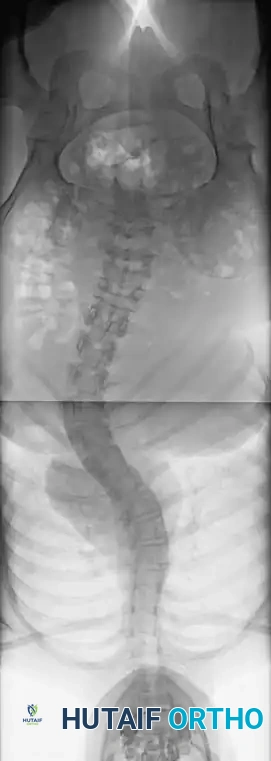

Fig. 38-22: Patient positioning on a Jackson table with hips in extension to maintain physiological lumbar lordosis.

Positioning on the Jackson Table

- Prone Positioning: The patient is carefully rolled prone onto an open-frame Jackson table (e.g., Mizuho OSI, Union City, Calif). The open frame is paramount as it allows the abdomen to hang free.

- Hemodynamic Optimization: Eliminating intra-abdominal pressure prevents compression of the inferior vena cava. This directly reduces venous engorgement within Batson’s epidural venous plexus, drastically minimizing intraoperative blood loss during exposure and pedicle cannulation.

Surgical Warning: When a patient is positioned prone with the hips flexed, physiological lumbar lordosis is artificially obliterated. If the planned fusion extends into the lower lumbar spine (L3, L4, or L5), it is imperative to elevate the knees and thighs so the hip joints are fully extended. This maneuver restores and locks in normal lumbar lordosis, which is critical for preventing postoperative flatback syndrome and adjacent segment disease.